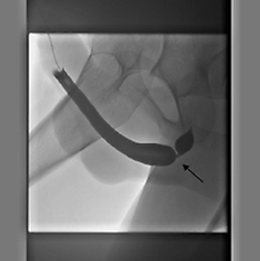

Röntgenonderzoek (retrograad urethrogram)

Het röntgenonderzoek is op de afdeling Radiologie of op de polikliniek Urologie. Er wordt een slangetje in het begin van uw plasbuis geplaatst. Door dit slangetje wordt contrastvloeistof in de plasbuis gespoten. Hierdoor wordt de binnenkant van de plasbuis gevuld. Met een röntgenapparaat wordt dan een foto van de plasbuis gemaakt. Door de vloeistof is een vernauwing goed te zien. Lees meer in de folder Retrograde urethragrafie.

Een röntgenfoto van de plasbuis met contrastvloeistof. Er is een vernauwing te zien bij de pijl. (Bron: Nederlandse Vereniging voor Urologie)